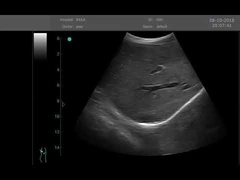

Kalite Portatif Ultrason tarayıcı, taşınabilir ultrason tarayıcı manufacturer from China